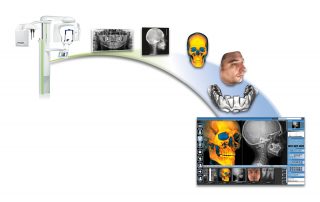

Planmeca ProMax 3D is a product family consisting of exceptional all-in-one units. All Planmeca CBCT units support three different types of 3D dental imaging – as well as panoramic, extraoral bitewing and cephalometric imaging. Planmeca is the first company to combine three different types of 3D data within one X-ray unit, ensuring these intelligent machines meet all maxillofacial imaging requirements. The ProMax family brings together a Cone Beam Computed Tomography (CBCT) image, 3D face photo and 3D model scan into one 3D image – using the same advanced software.

Premium image quality

Comprehensive imaging software

Planmeca Romexis® is the leading software platform for dentistry. It provides a rich set of tools to meet the imaging requirements set by any dental facility – from a small clinic to a large hospital. The software supports all 2D and 3D dental imaging as well as CAD/CAM workflows with its extensive range of tools.